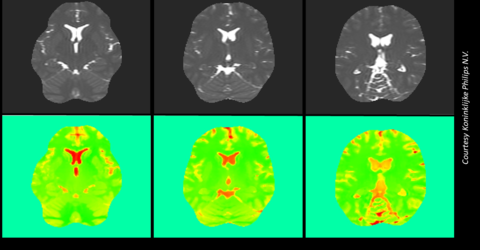

Six pictures showing a human brain scan. Three images in upper row showing black and white pictures of the brain and below these the corresponding EPT images in green with orange indicating tissue sub-types

Quantifying the uncertainty of Electric Properties Tomography in medical imaging